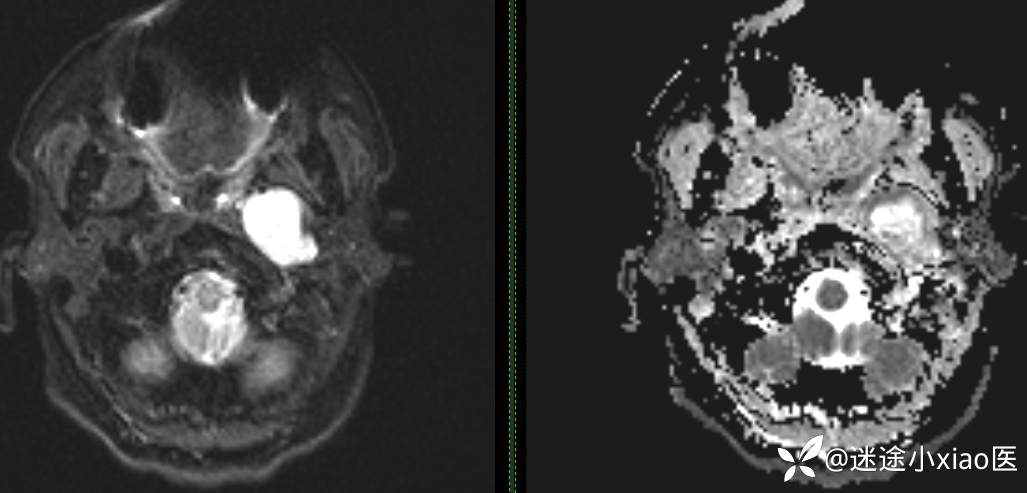

头颈组17:颈静脉孔区占位,副神经节瘤?神经鞘瘤?脑膜瘤?

患者性别:女

患者年龄:57岁

主 诉:  声音嘶哑进食困难伴左侧颌部麻木半年

现病史:  【患者半年前无明显诱因出现声音嘶哑,进食困难,只能进食糊状食物,伴有恶心呕吐,无明显头痛头晕,未加重视。